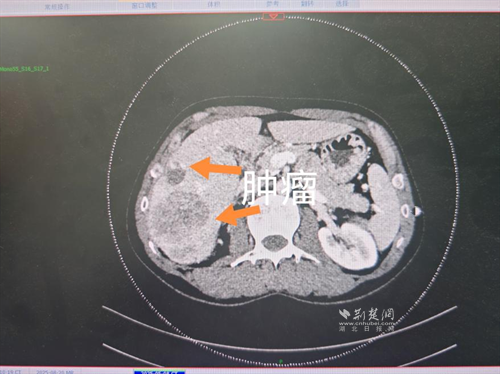

經(jīng)過(guò)肝膽外科牽頭組織的多學(xué)科MDT會(huì)診,團(tuán)隊(duì)確認(rèn)其適合接受當(dāng)前國(guó)際先進(jìn)的釔90樹(shù)脂微球選擇性內(nèi)放射治療。治療僅一個(gè)月后,患者病灶即從10cm縮小至6cm;術(shù)后六個(gè)月復(fù)查顯示,病灶體積進(jìn)一步縮小近40%,影像學(xué)檢查提示完全緩解,臨床分期成功轉(zhuǎn)化,達(dá)到手術(shù)切除標(biāo)準(zhǔn)。